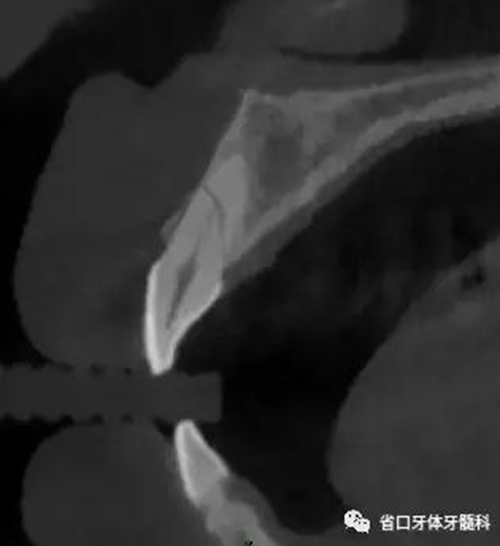

圖3:11術(shù)前CT

CBCT:11、21頸部以下均見(jiàn)一完全性折裂線,兩牙折裂線均位于頜骨內(nèi)且斷端移位不明顯,相應(yīng)唇側(cè)骨板亦見(jiàn)斷裂且輕度移位。